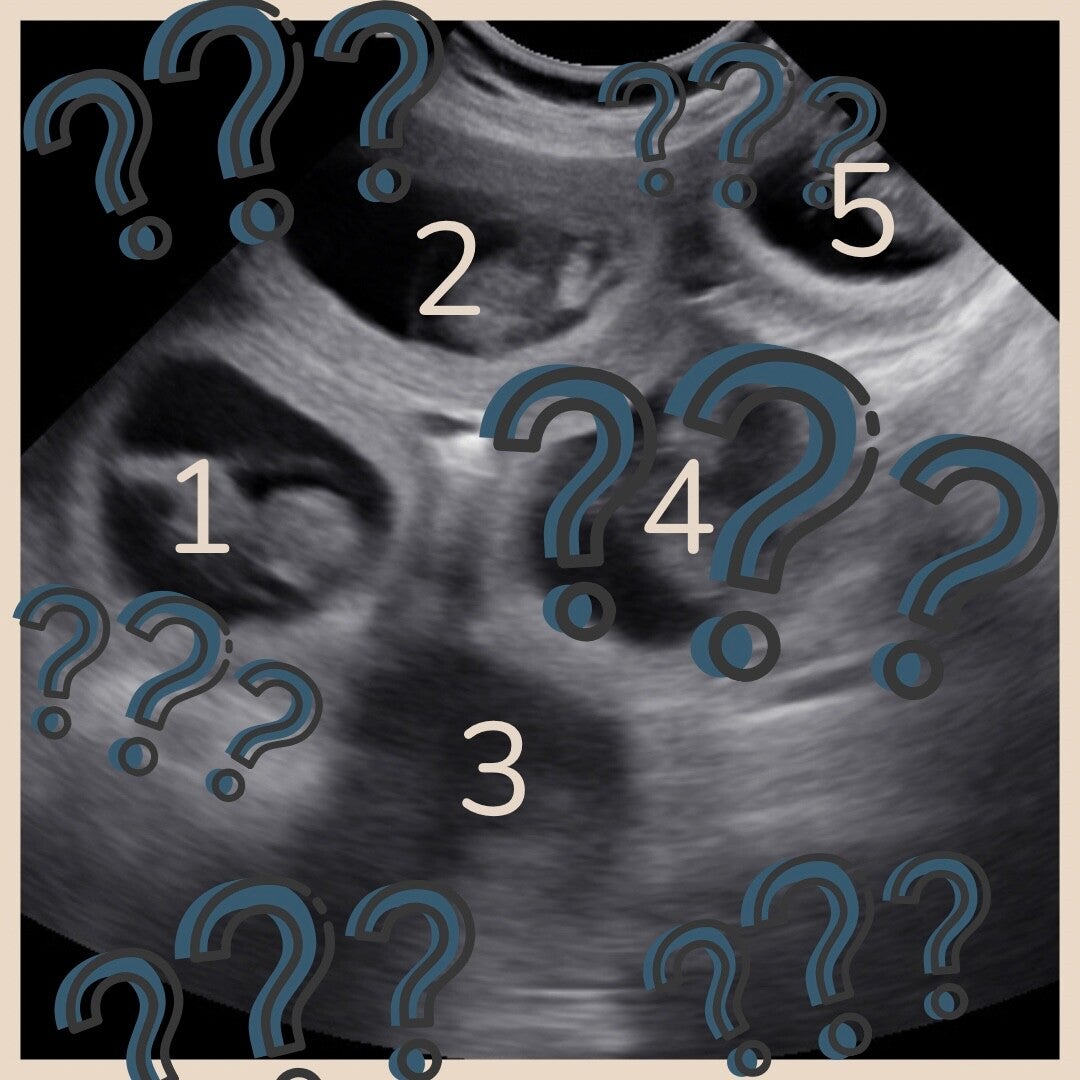

Tellen van het aantal pups/kittens tijdens de echo

Regelmatig krijg ik de vraag of er tijdens de echo ook gekeken wordt hoeveel pups/kittens er in de buik zitten en hoe nauwkeurig deze telling is. Hieronder leg ik uit welke factoren invloed hebben op de nauwkeurigheid van de telling.

Op dag 25 t/m 28 gaat het zeker lukken om de dracht vast te stellen, maar de kans op resorptie neemt pas daarna echt af. Beter is het dus om te wachten tot dag 30 en bij grote honden zelfs liever tot dag 32 (bij grote honden liggen de pups dieper in de buik en dan is het handig als ze nét wat groter zijn). Na dag 35 wordt het tellen weer moeilijker, omdat pups die in de diepte liggen (achter een andere pup) gemist kunnen worden.

•  Grote aantallen

Hoe meer pups er in de buik zitten hoe moeilijker het wordt. De kans dat je een pup mist of dubbel telt wordt groter.